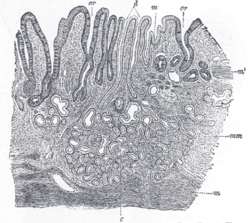

Section of duodenum of cat. X 60. (Muscularis mucosae labeled at right, third from the top.)

The lamina muscularis mucosae (or muscularis mucosae) is a thin layer (lamina) of muscle of the gastrointestinal tract, located outside the lamina propria mucosae and separating it from the submucosa. It is present in a continuous fashion from the esophagus to the upper rectum (the exact nomenclature of the rectum’s muscle layers is still being debated). A discontinuous muscularis mucosae–like muscle layer is present in the urinary tract, from the renal pelvis to the bladder; as it is discontinuous, it should not be regarded as a true muscularis mucosae.

The muscularis mucosae is composed of several thin layers of smooth muscle fibers oriented in different ways which keep the mucosal surface and underlying glands in a constant state of gentle agitation to expel contents of glandular crypts and enhance contact between epithelium and the contents of the lumen.